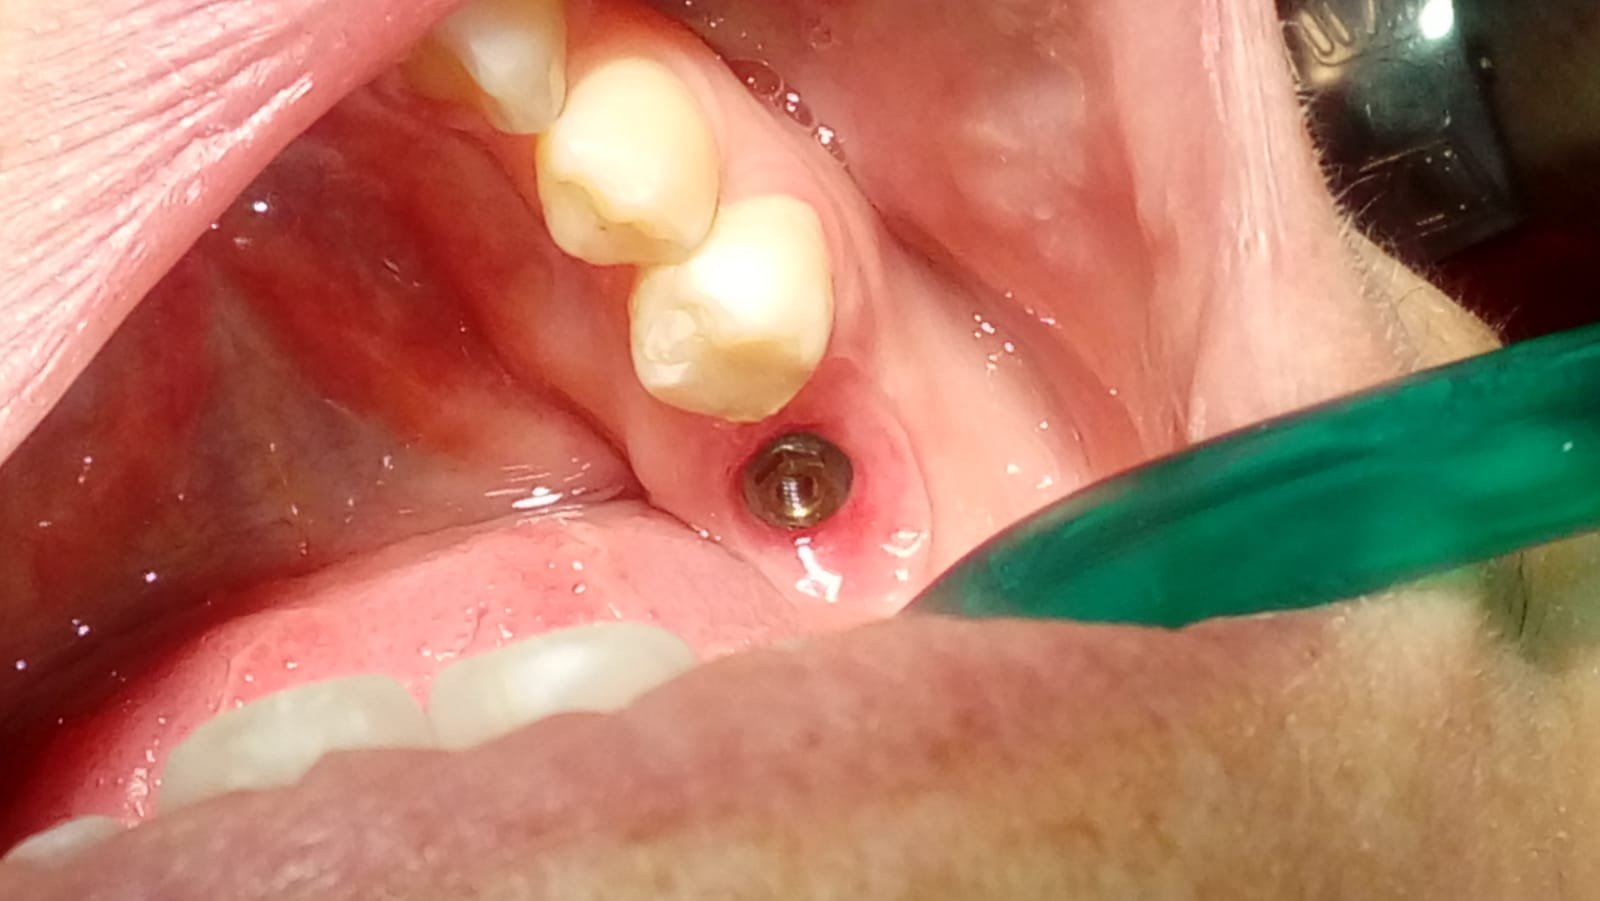

IOI 41 colocado en España (Zona Levante)hace unos 3 años. La métrica del destornillador es 1.2 hexagonal ¿Alguien canta bingo?